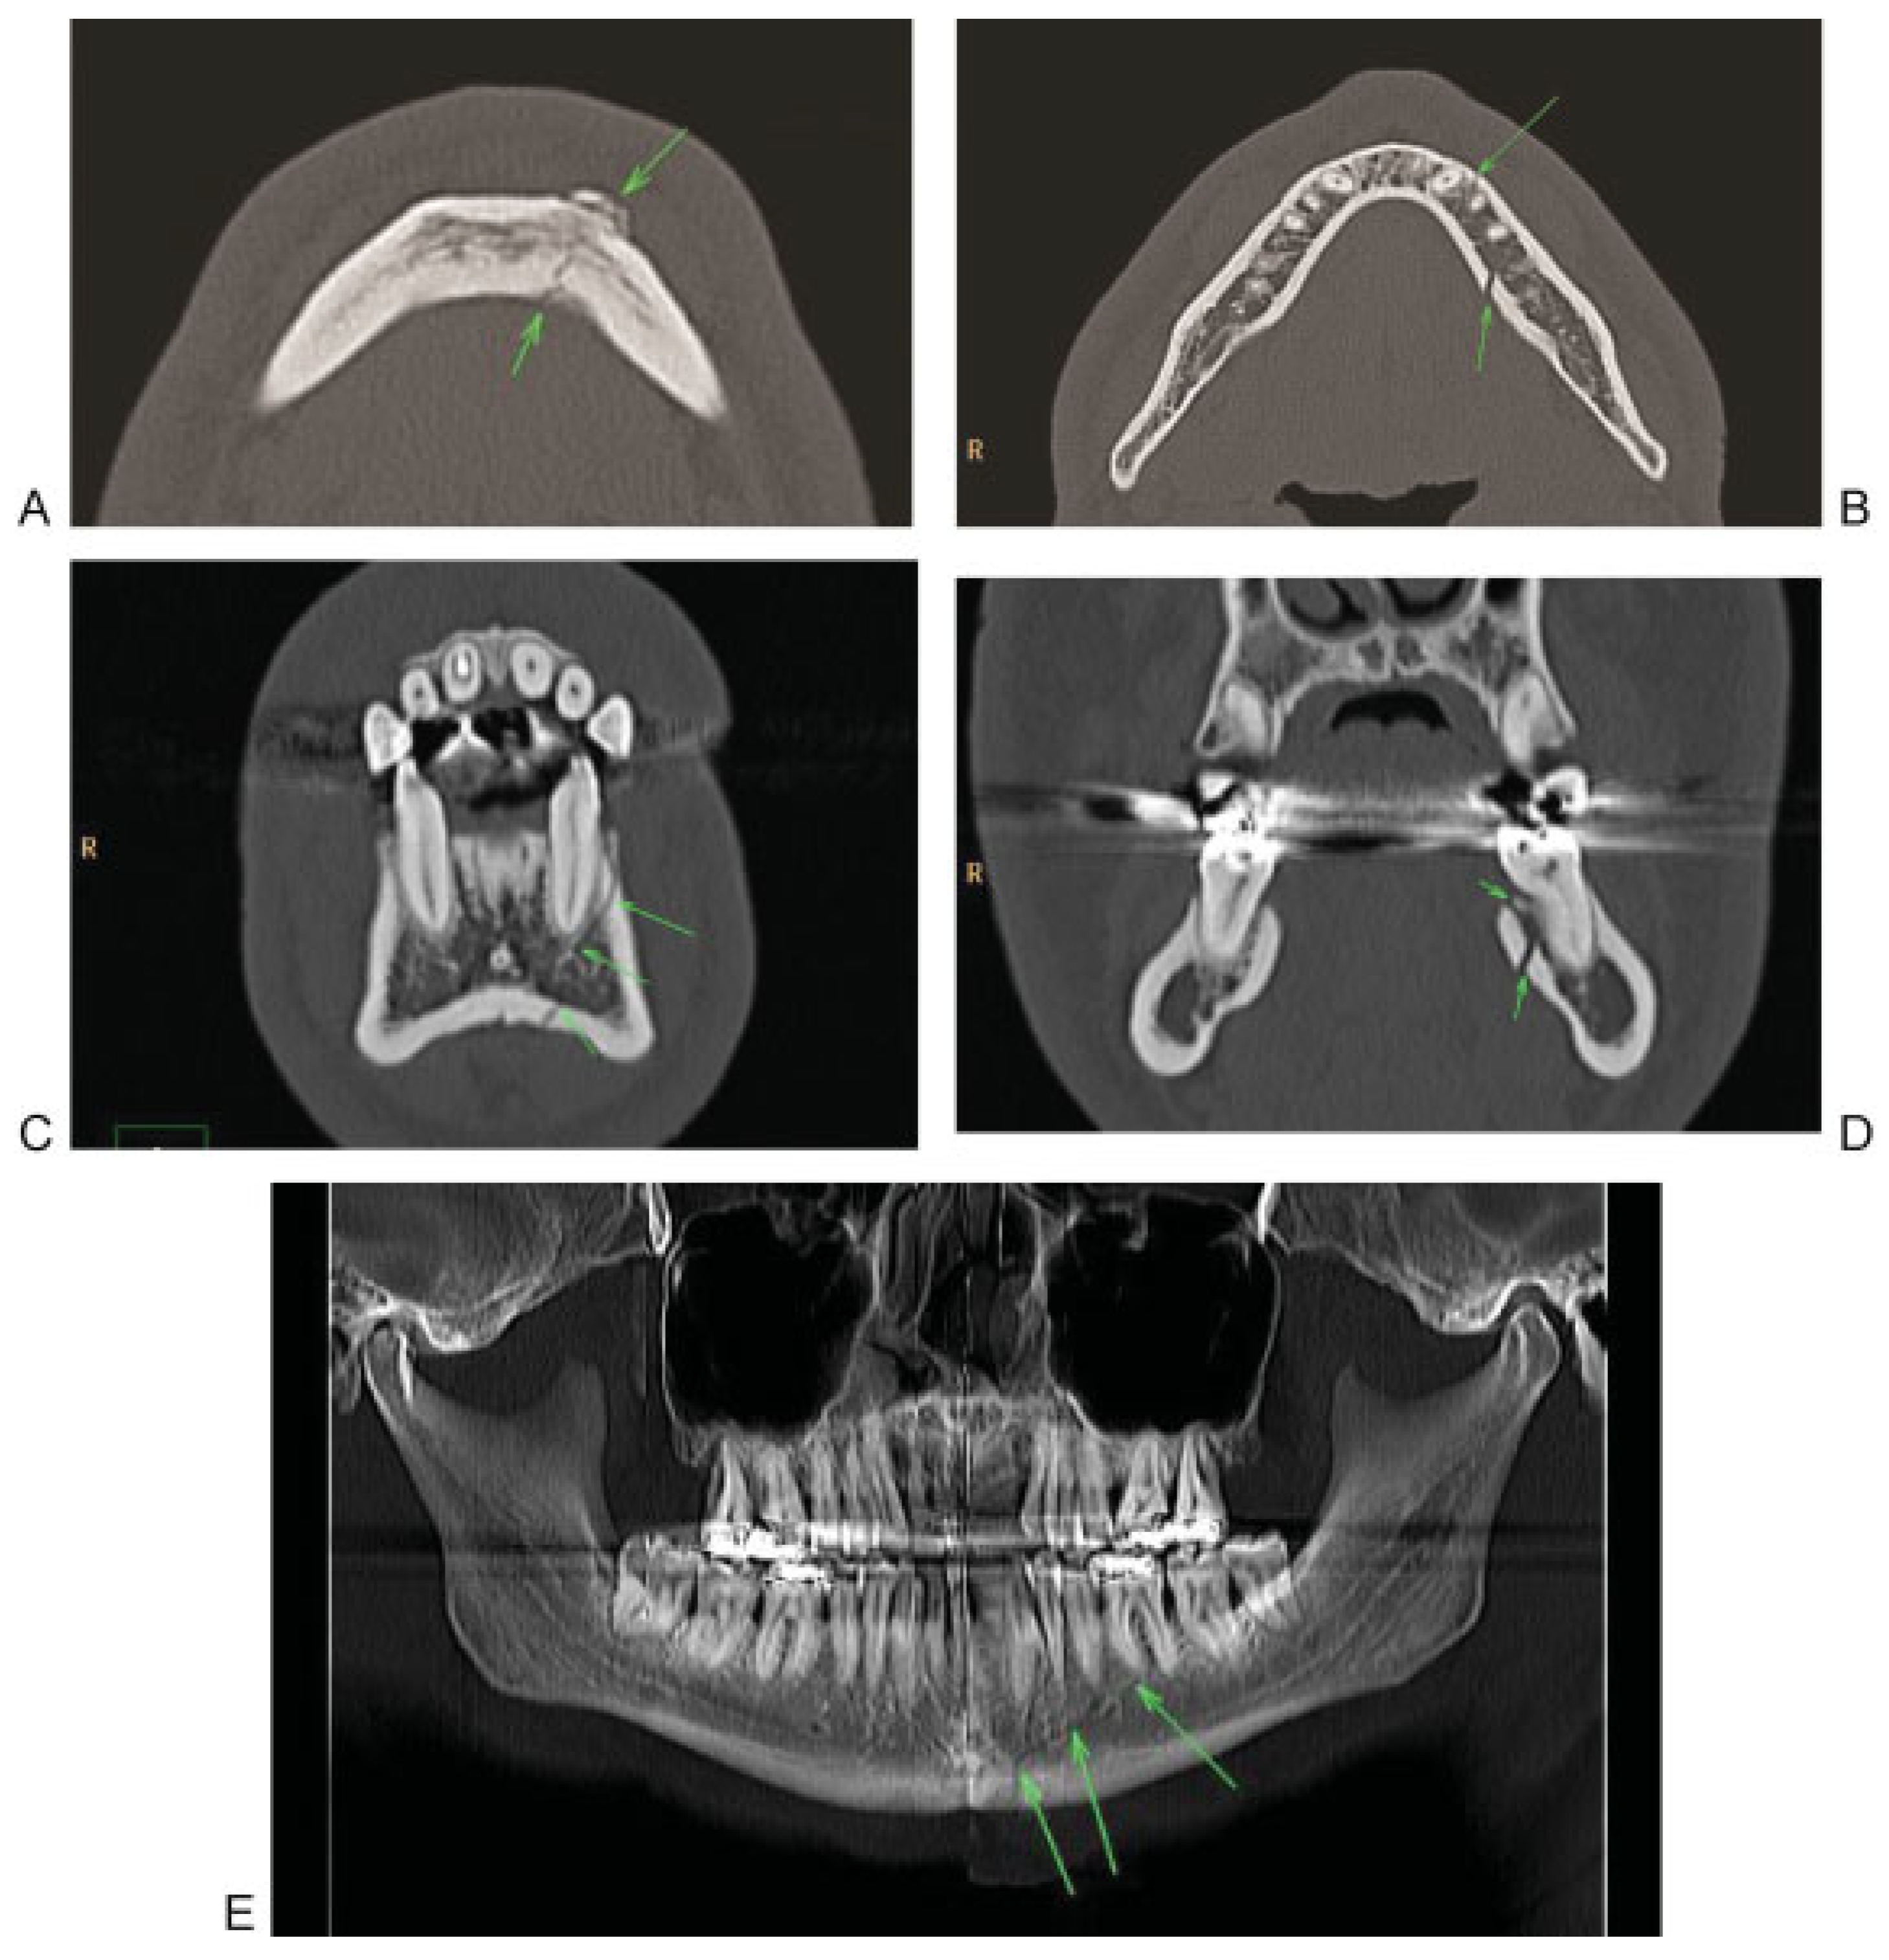

Systematic evaluation of the midface in CT begins with the evaluation of axial slices from caudal to cranial (Figure 2A–C) to detect direct fracture signs, especially in the lower central midface (including alveolar process, caudal part of nasomaxillary buttress), intermediate central midface (including anterior sinus walls), upper central midface (including frontal process maxilla, lacrimal bone and nasal bones). In the axial plane the zygoma and zygomatic arch are evaluated with all its relationships to the central midface. Subsequently, the orbital rims as well as lateral and medial orbital walls are assessed. In a second step coronal 2D reconstructions (Figure 2E,F) are checked for the integrity of the nasomaxillary buttress in the lower and intermediate central midface regions, the frontal process of the maxilla and the nasal bones in the anterior coronal reconstructions (Figure 3). The integrity of the palate and the pterygoid plates should also be checked in the coronal plane, which ideally should be perpendicular to the palate. Furthermore the medial orbital walls, the orbital floors and orbital roofs are well detected in the coronal plane. The orbital apex regions are search for integrity, especially of the optic nerve canal. Additional 2D reconstructions for the orbital floor through the axis of the intraorbital nerve may be useful in detecting displaced fractures with muscle entrapment or retrobulbar hematoma. 3D CT reconstructions may not add significant information for level 2 classification (Figure 2G–I).

Figure 3. Systematic analysis of a midfacial fracture in coronal reconstruction. (A) Evaluation of the upper central midface with nasal bone and maxillary frontal process fractures on the right side (B) Fracture of the anterior part of the medial orbital wall (arrows) and linear fracture of the orbital floor on the right side.